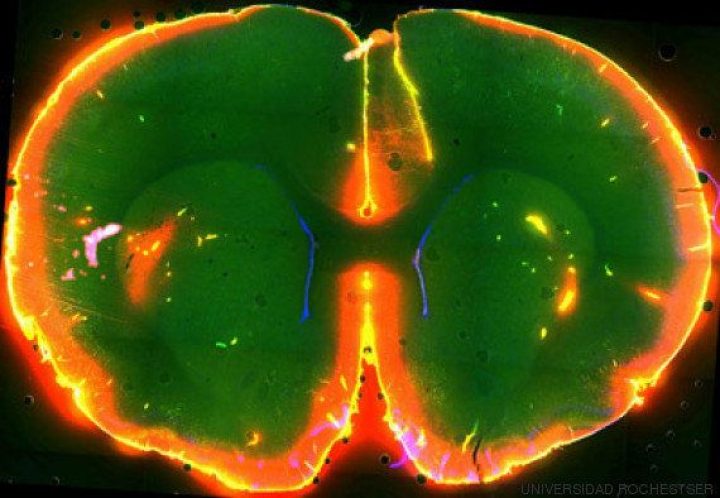

En 2013, un estudio publicado en la revista Science y dirigido por la neuróloga del Centro Médico de la Universidad de Rochester (EEUU) Maiken Nedergaard reveló que los canales entre las neuronas de los ratones crecen un 60% durante el sueño, y que este ahuecamiento se aprovecha para drenar las toxinas que se acumulan en esos espacios hacia el líquido cefalorraquídeo, el fluido que baña el cerebro y la médula espinal. En otras palabras, los científicos descubrieron que durante el sueño el cerebro tira de la cadena, eliminando residuos indeseables como la proteína beta-amiloide que es característica de la enfermedad de Alzheimer. El hallazgo fue tan revolucionario que mereció un puesto entre los diez avances del año para la revista Science.